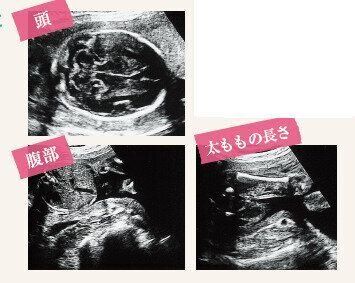

3. 【医師監修】産科医がビジュアルで解説します!「超音波写真(エコー写真)の見方」ガイド